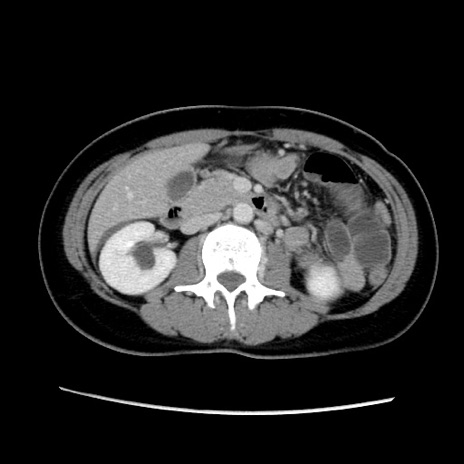

症例39(横断像)

【症例】40歳代女性

【主訴】上下腹部痛

【現病歴】2日目から下腹部痛あり。夜間は痛みで眠れなかった。昨日より上腹部痛と下痢が出現。臥位で痛みは軽快したため、休んでいた。本日になって臥位でも立位でも痛みが強くなってきたため救急要請。

【既往歴】子宮内膜症

【身体所見】部:平坦・軟、左上下腹部に圧痛あり、反跳痛あり。

【データ】WBC 21800、CRP 26.78